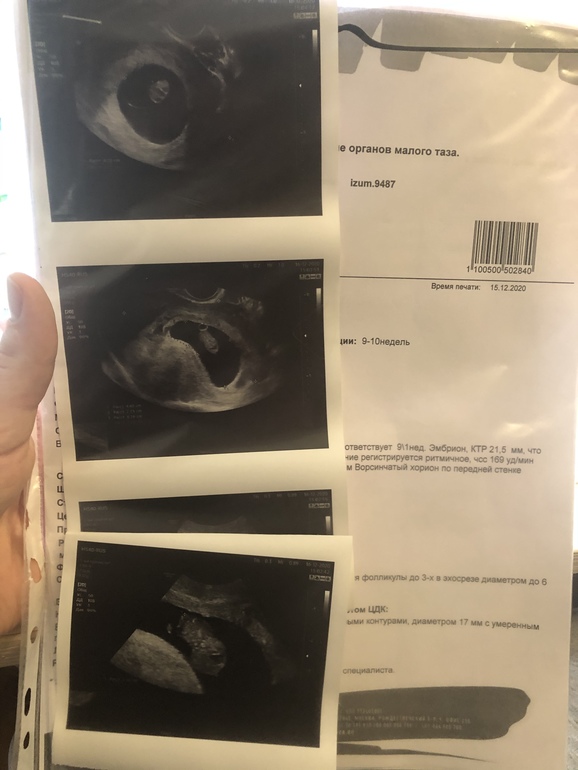

Сходила сегодня на узи . Соответствуем сроку .

Сходила сегодня на узи . Соответствуем сроку .

Фото УЗИ нужно 6-7 недель, не позже, тогда смотрят по этому методу